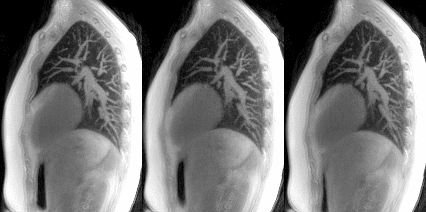

3D MRI lung dynamics for free, thoracic, and diaphragmatic breathing